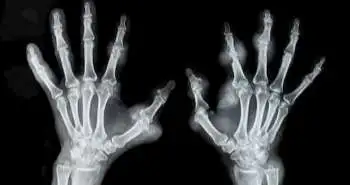

In pregnancy, several changes in the immune system take place which in turn affects the course of rheumatoid arthritis (RA). Hissay Aljary et al. evaluated in their cohort study that pregnant women are at a greater plausibility of adverse maternal and neonatal outcomes and they should also be made well-informed of these risks.

The current study aimed to estimate if there is a greater risk of adverse maternal and neonatal outcomes in pregnant women suffering from RA.

Of the total 8,417,607 births, 6068 were among women suffering from RA for an overall incidence of 72 per 100,000 births. Over the 10-year duration of study, a stable increase in reported RA in pregnancy from 47 to 100 per 100,000 was noted. Women with RA were more likely to initiate pre-eclampsia/eclampsia, gestational diabetes, to present with preterm premature rupture of membranes (PPROM), to experience placental abruption and placenta previa, and to deliver by caesarean section. Wound difficulties and thromboembolisms were associated with postpartum, RA-complicated pregnancies. Congenital anomalies, small for gestational age and preterm birth were more frequent in neonates of women with RA.

There is a higher risk of adverse maternal and neonatal outcomes in pregnant women with RA. The risks should be well informed to these women.